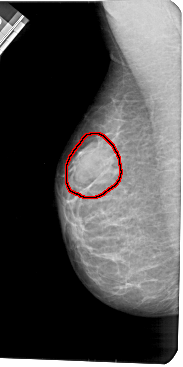

FILE: A_1419_1.LEFT_MLO.OVERLAY

TOTAL_ABNORMALITIES 1

ABNORMALITY 1

LESION_TYPE MASS SHAPE OVAL MARGINS OBSCURED

ASSESSMENT 4

SUBTLETY 4

PATHOLOGY BENIGN

TOTAL_OUTLINES 1

BOUNDARY